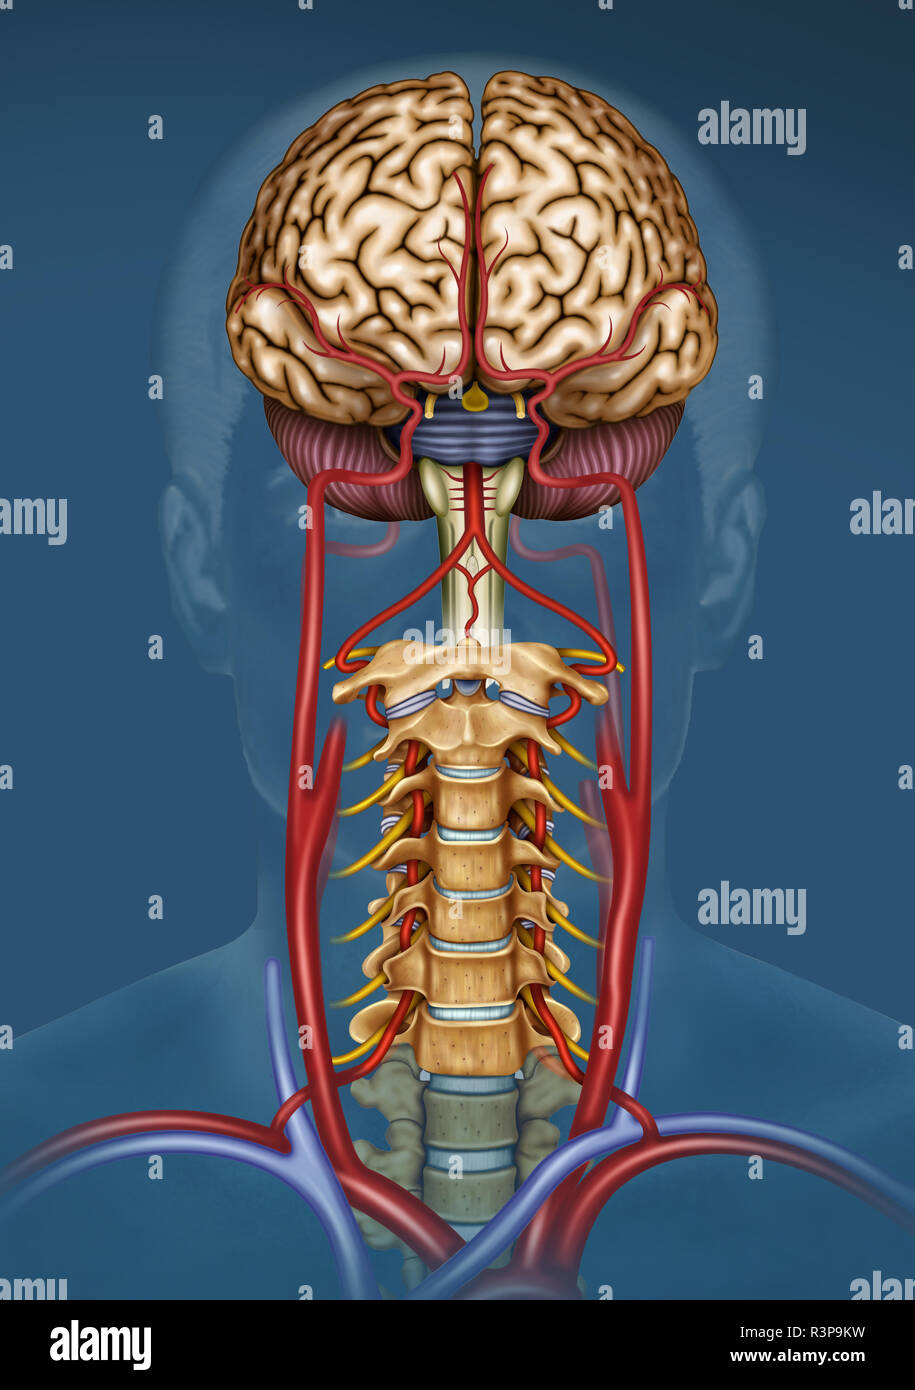

RFR3P9KW–Illustration der Blutversorgung des Gehirns. Das Gehirn hat wenig Kapazität, Nährstoffe zu speichern, aber es braucht eine hohe Versorgung mit Sauerstoff und Glukose.

RMJE9NWM–Dieses anatomische Bild zeigt die Arterien unter dem Gehirn, einem wichtigen Teil des menschlichen Kreislaufsystems. Die Arterien sind dafür verantwortlich, das Gehirn mit Blut zu versorgen und seine Funktion zu gewährleisten. Die Nahansicht hilft beim Verständnis ihrer Struktur und Rolle für die Gesundheit und Funktion des Gehirns.